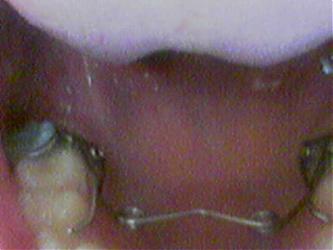

وهذه صورة التقويم

نوع الملف: jpg 20070808176.jpg‏ (10.5 كيلوبايت, المشاهدات 51)

نوع الملف: jpg 20070808177.jpg‏ (11.1 كيلوبايت, المشاهدات 54)

يبدو لي من الوهلة الأولى أنه عندك الأطباق غير صحيح لأن الدكتور بهذا الجهاز يحاول تبعيد الأسنان حتى يحصل على إطباق صحيح .

على كلاً هذه الأمور لا يعرفها بشكل جيد سوى دكتور التقويم الذي درس الحالة فهو عنده فكرة موسعة عن الحالة من خلال المقاسات والصور الشعاعية